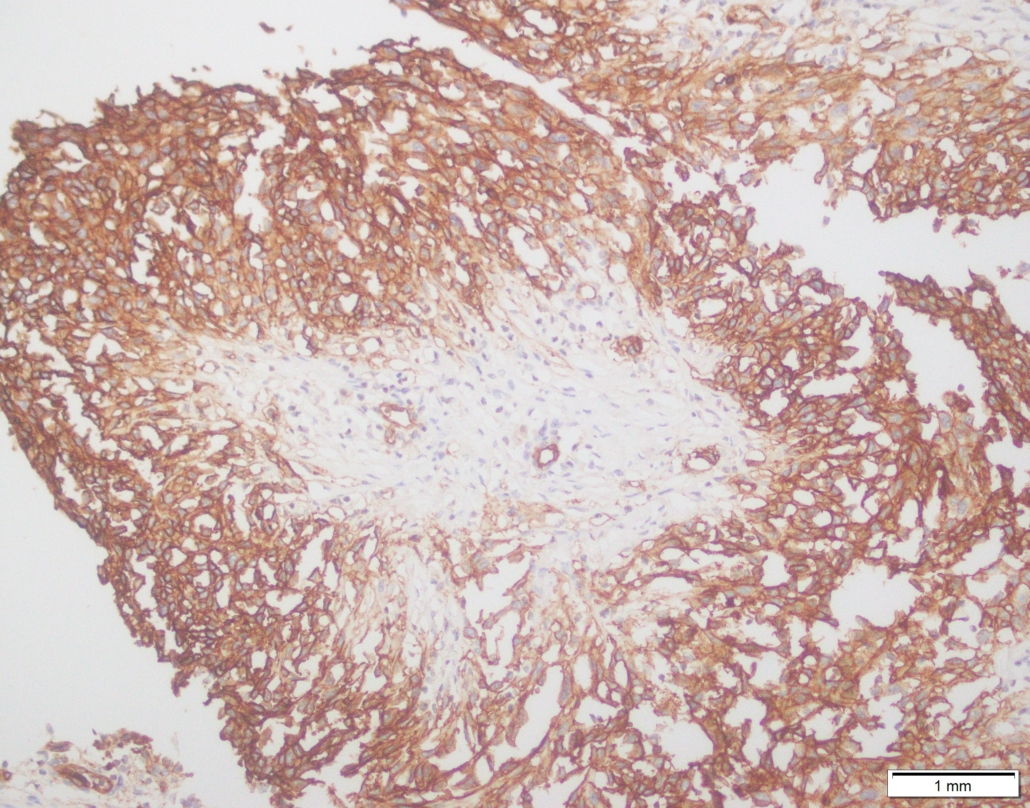

Case 03

Case presented by Dr Shaarif Bashir, FCPS (PAK), Shaukat Khanum Memorial Cancer Hospital and Reserach Centre, Pakistan